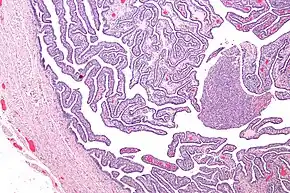

Definitive criteria include histopathologic evidence of endometritis, thickened filled Fallopian tubes, or laparoscopic findings. Gram stain/smear becomes definitive in the identification of rare, atypical and possibly more serious organisms.[22] Two thirds of patients with laparoscopic evidence of previous PID were not aware they had PID, but even asymptomatic PID can cause serious harm.